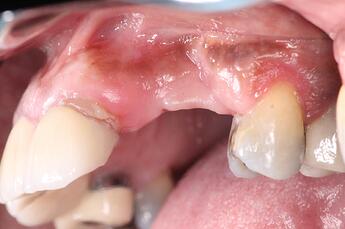

Missing 10 & 11 were extracted a year ago. Implants were placed, but healed terribly. The failed implants were removed, and now the site presents with significant bone loss, and severe resorption.

A Full thickness flap was reflected to expose the defect. You can see how severe the defect is, in both the vertical and horizontal dimensions. This is going to be a challenging GBR procedure, and we wanted to use the best materials at our disposal to encourage bone growth.